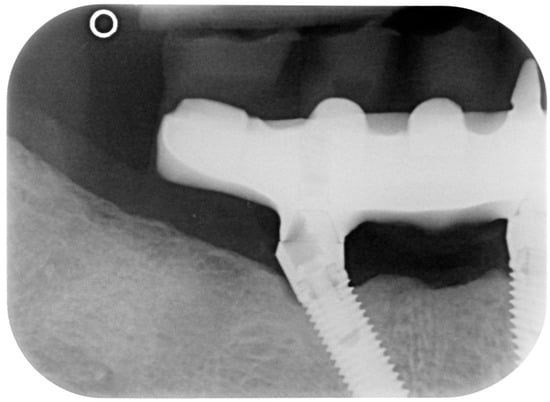

Figure 10.

X-ray of 3.5 dental implant in patient before treatment.

Figure 13.

X-ray of 3.5 dental implant in patient in 6 months after treatment.